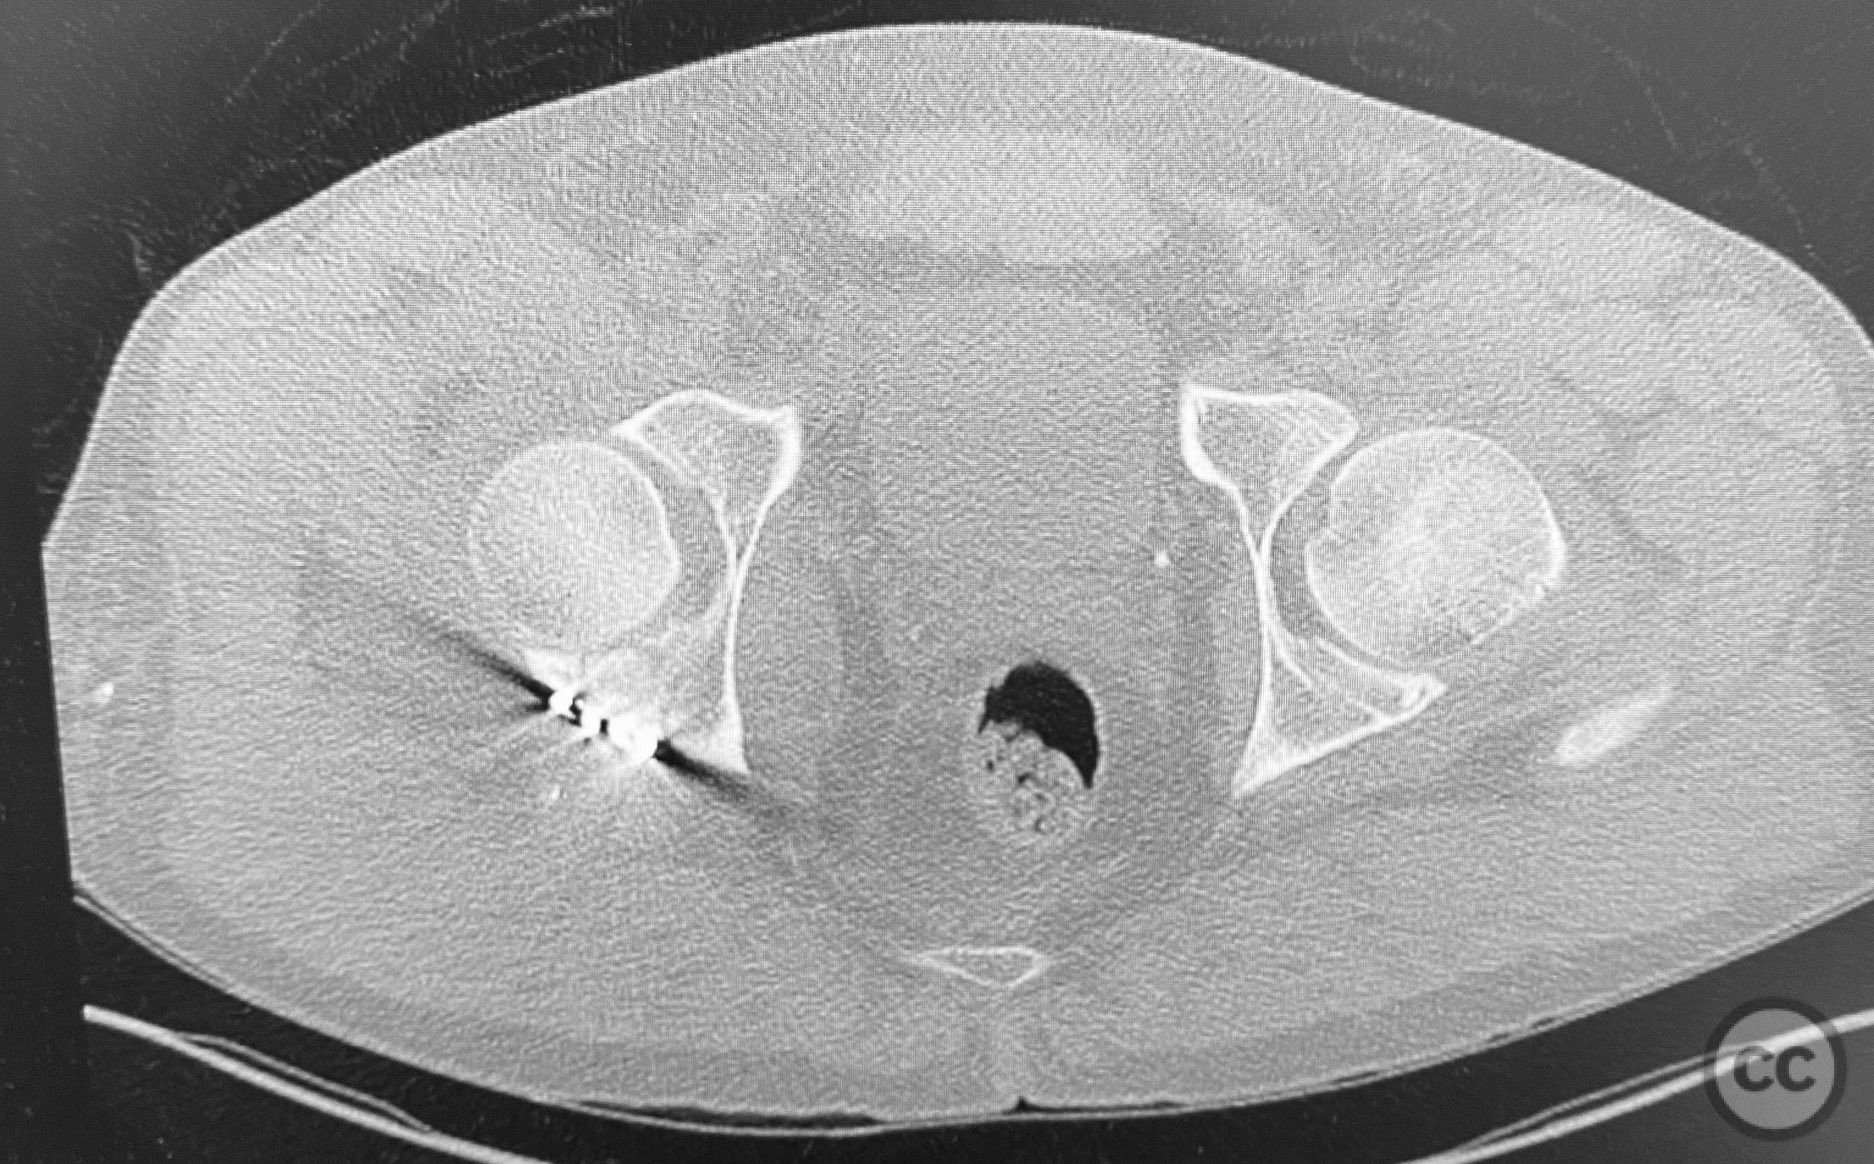

Clinical and radiological findings:  The patient sustained a comminuted acetabular fracture with multiple chondrocancellous articular fragments. The injury pattern is consistent with an AO/OTA 62-B3 (both column) acetabular fracture. Initial radiographs and computed tomography demonstrated displaced intra-articular fragments with associated segmental bone loss and wall involvement. No neurovascular compromise was documented.

Planning remarks:  The preoperative plan involved an extensile approach to the acetabulum, with the intention to carefully extract all chondrocancellous fragments for ex vivo cleansing, followed by dense packing of allograft bone grit into metaphyseal defects to support articular reconstruction. Sequential reduction of articular fragments was planned, followed by reduction and fixation of the acetabular wall using plate osteosynthesis.

All chondrocancellous fragments were meticulously removed from the wound and cleansed of hematoma and debris. Dense allograft bone grit was packed into metaphyseal defects to provide subchondral support. Each articular fragment was anatomically reduced and provisionally stabilized. The posterior wall was then reduced and definitive fixation achieved using contoured reconstruction plates. Attention was paid to restoring the congruity of the acetabular dome and maintaining anatomic reduction throughout the sequence.